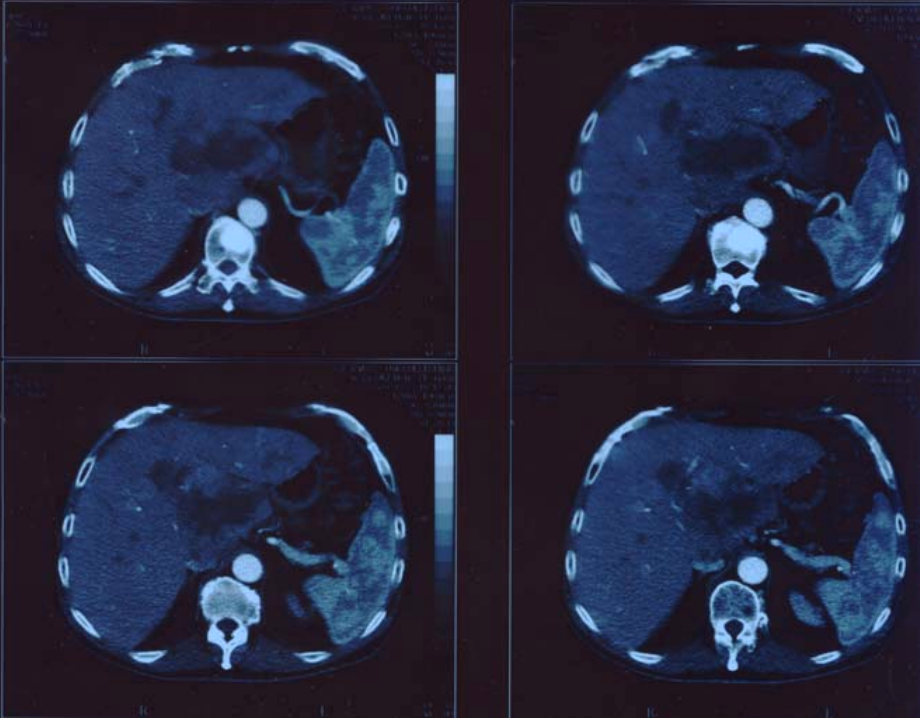

Figure1